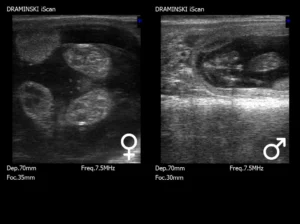

En mi trabajo reproductivo diario con novillas, me baso principalmente en programas hormonales adaptados al rebaño específico. Una vez que la novilla alcanza el peso y el tamaño adecuados, realizamos el primer examen ecográfico e introducimos al animal en el programa. En cuanto a la inseminación artificial, existen varios métodos de cría eficaces. A menudo, confiamos en la observación del celo, pero el éxito de este método depende del factor humano, que desgraciadamente suele fallar.

Tras la inseminación, el primer control de gestación se realiza entre los días 26 y 30, y se vuelve a confirmar en el tercer mes.